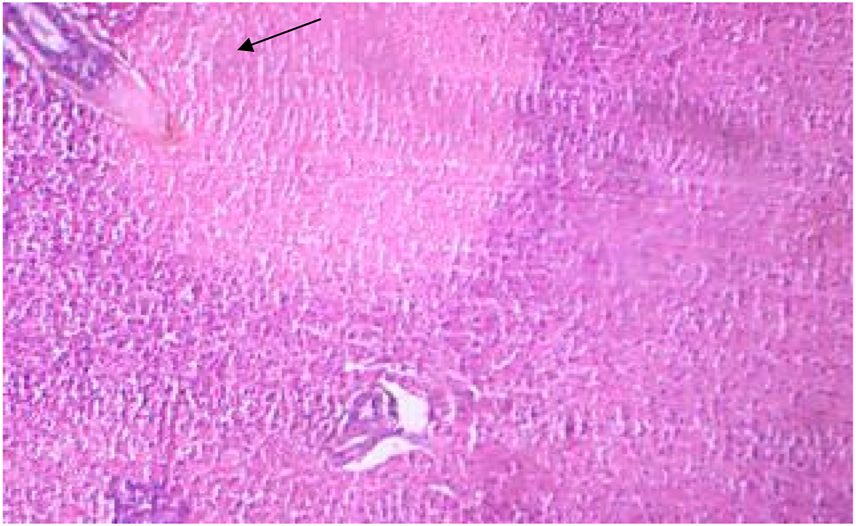

Gill

After 96 h of treatment, there was a marked variation between the control and treated gill tissues. The gill arches of the control group (Figure 1) showed a normal arrangement pattern, while the treated gill sections Figures 6, 7 exhibited congestion and epithelial proliferation. (Essien et al., 2013) have found that exposing Malpighian cells to chemical irritation leads to an accumulation of cells at the leading edge of the secondary lamella, resulting in the epithelial proliferation of secondary gill lamellae. This indicates that DCM has a direct effect on gill filaments as a cytotoxic and irritating substance, resulting in the proliferation and fusion of secondary lamellae.

FIGURE 6

Control gills showing primary and secondary lamellae.

FIGURE 7

Treated gills section showing epithelial proliferation and congestion.

Moreover, gills are important not only for gaseous exchange but also for the osmoregulation and excretion of toxic waste products (Basha and Rani, 2003). Thus, any harm to the gills leads to impairment of these vital functions, revealing respiratory distress, impaired osmoregulation, and retention of toxic wastes. Histopathological studies conducted in goldfish have reported a fusion of the gill filaments due to toluene, suggesting a similar effect in gills due to other volatile organic compounds (Pandey et al., 2008). A similar effect was also seen in the gill samples of carp exposed to hexachlorocyclohexane (Cooley et al., 2001). Bhanot and Hundal, 2020 also reported similar observations of cytotoxicity in gills during the assessment of treated and un-treated polluted wastewater on Labeo rohita; they observed an increase in cytotoxicity upon an increase in the concentration of wastewater.